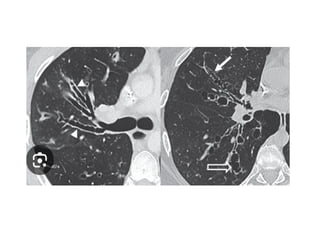

 Tomografía axial

computarizada de tórax

Complementarios:  Hematología completa: Anemia leve  Leucocitosis  Neutrofilia  Linfocitosis  Eosinofilia  Tomografía axial computarizada de tórax  Test de esputo con antibiograma  Proteína C reactiva: > 5mg/L  Velocidad de sedimentación globular: >10mm/h